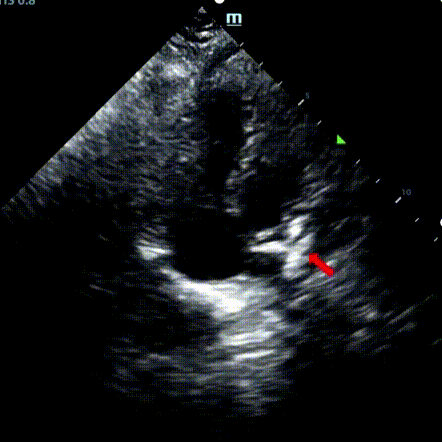

Se trató a un varón de 9 años de edad con ASD secundario (7,5-7,9mm) usando un oclusor de 12mm BDASD-I MemoSorb y un sistema de administración de 12F. No se observaron complicaciones ni comorbilidades antes del procedimiento.

Serial echocardiographic follow-ups showed stable device position and favorable cardiac remodeling. Gradual degradation confirmed the occluder's long-term safety and efficacy.